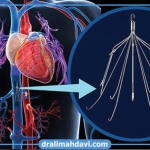

رادیولوژی مداخله ای (اینترونشنال)

رادیولوژی مداخلهای، یک رشته پزشکی پیشرفته است که از فناوریهای

دکتر علی مهدوی متخصص رادیولوژی (تصویربرداری)، فلوشیپ اینترونشنال رادیولوژی و استادیار رادیولوژی دانشگاه علوم پزشکی شهید بهشتی در این زمینه هستند که فعالیتهای گوناگون علمی و تحقیقاتی در این حوزه انجام دادهاند.